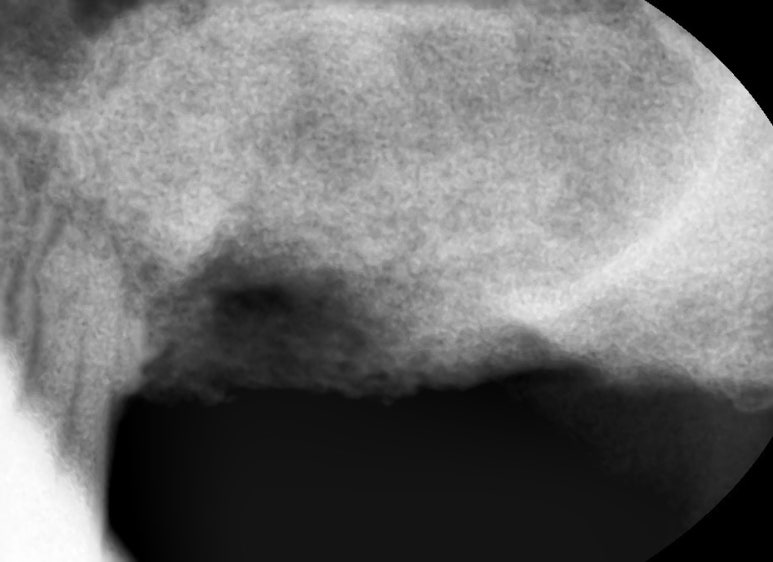

그래서 임플란트 픽스쳐를 제거하고,

옆의 흔들리는 치아 하나 까지 발치하여

임플란트 재수술은 임플란트 2개를 심고 머리 3개를 만들어 완성하였습니다.